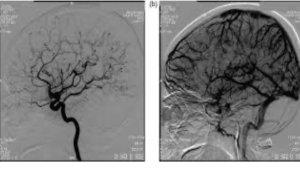

| Cek Penyebab Pusing Berkepanjangan dengan DSA Cerebral di Mayapada Hospital Surabaya |

| Cegah Stroke dengan Aman Tanpa Nyeri di Mayapada Hospital Surabaya |

| Gangguan Otak Penyebab Stroke Berhasil Diatasi, Begini Penjelasannya! |